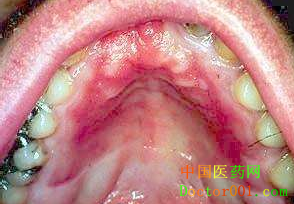

手术方法 修复时,基底膜面向外。舌、唇部等粘膜缺损,早期采用间断缝合加反包扎,后期病例取消反包扎。仅在脱细胞异体真皮中部缝合数针,将其固定在基部肌组织上。但粘膜转折部位如前庭沟处的缺损,仍常规进行反包扎。牙龈瘤手术切除后的牙槽突黏膜缺损,早期采用反包扎,后期也仅进行间断缝合,但必须保证脱细胞异体真皮紧贴骨面。鄂部创面因呈突向上放的穹窿状,为保证脱细胞异体真皮与骨面充分接触,必须采用反包扎。 关于脱细胞异体真皮(北京桀亚莱福提供)移植后是否必须进行加压包扎,目前存在不同的观点。在皮肤烧伤治疗方面,通常比较强调脱细胞异体真皮移植后的加压包扎和固定,并且认为良好的包扎、固定是脱细胞异体真皮在烧伤创面成活的前提条件。但在口腔上皮缺损修复方面,脱细胞异体真皮移植后仅作间断缝合,其愈合过程和成活情况与反包扎病例并无明显区别。因此,有理由相信,只要能保证脱细胞异体真皮与基底组织充分接触,加压包扎或反包扎并不是脱细胞异体真皮口内移植后成活的必要条件。 本研究还初步探讨了脱细胞异体真皮在前庭沟加深术中的应用,从组织愈合和临床效果来看,该方法具有可行性。综上所述,脱细胞异体真皮口内移植欧成活率高,创面覆盖效果好,无瘢痕形成,是较理想的口内上皮缺损修复材料。但在临床应用中,应特别注意修复后的组织收缩,避免局部收缩对移植区软组织活动度和相关功能造成不利影响。 (责任编辑:Doctor001) |